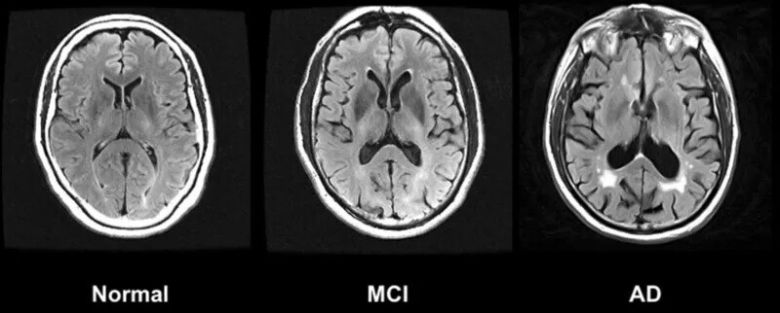

왼쪽부터 정상인, 경도인지장애(MCI), 알츠하이머병(AD)의 뇌. 위키미디어 코먼스